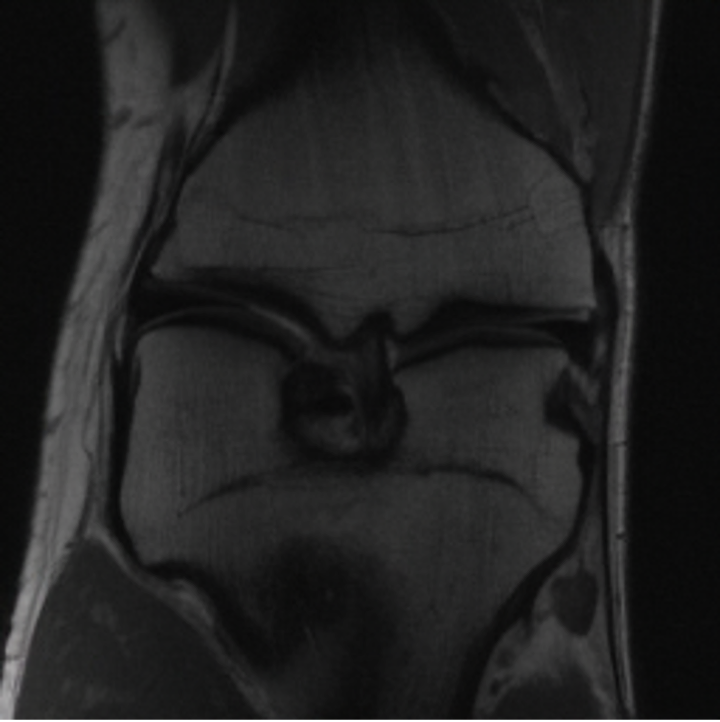

5.3 Out-of-Domain Generalisation

One way to test the generalization capability of the trained X-Diffusion is to test it on a completely different domain from an MRI dataset not seen during training. We report the single-slice results on NYU fastMRI [37, 82], a knee MRI dataset, using the X-Diffusion trained on the BRATS brain MRIs. The results are shown in Figure 9 and Table 2. It shows how successfully X-Diffusion is able to generate knee MRIs from a single image, despite not seeing knees at all in training. To qualitatively assess how realistic our generated 3D volumes were (produced from a single slice), we gave 20 generated examples alongside their real MRI counterparts to an expert orthopaedic surgeon. He was then asked to identify the real example from a given pair. The surgeon identified with certainty only 10 real knee MRIs out of 17, while could not decide on the remaining 3 of the 20 MRI pairs. This further validates the generated out-of-domain MRIs.